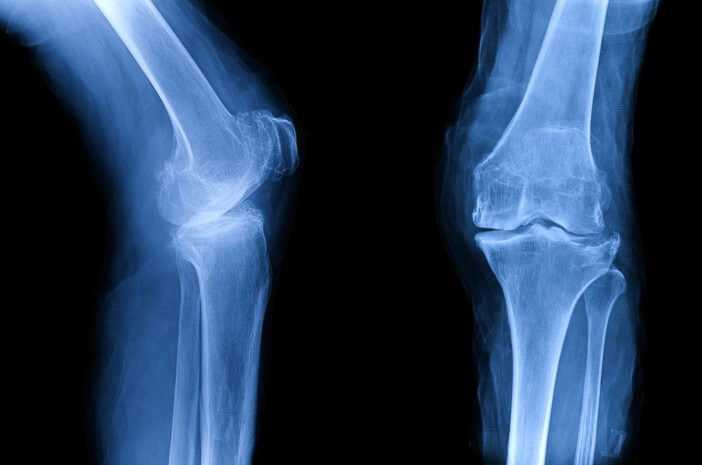

3. Prosedur pemeriksaan lanjutan dengan pencitraan

Sampai ke tahap ketiga, biasanya akan dilakukan ketika dokter menemukan ada indikasi bahwa penderita memang positif menderitanya. Prosedur pencitraan merupakan hal wajar untuk dilakukan agar bisa mengkonfirmasi diagnosis sebelumnya.

Tes pencitraan yang dimaksud bukan hanya foto rontgen karena bisa juga melalui USG kehamilan ketika ada risiko janin dalam kandungan memiliki potensi mengalaminya juga. Jadi pemeriksaan juga bisa dilakukan pada calon bayi.